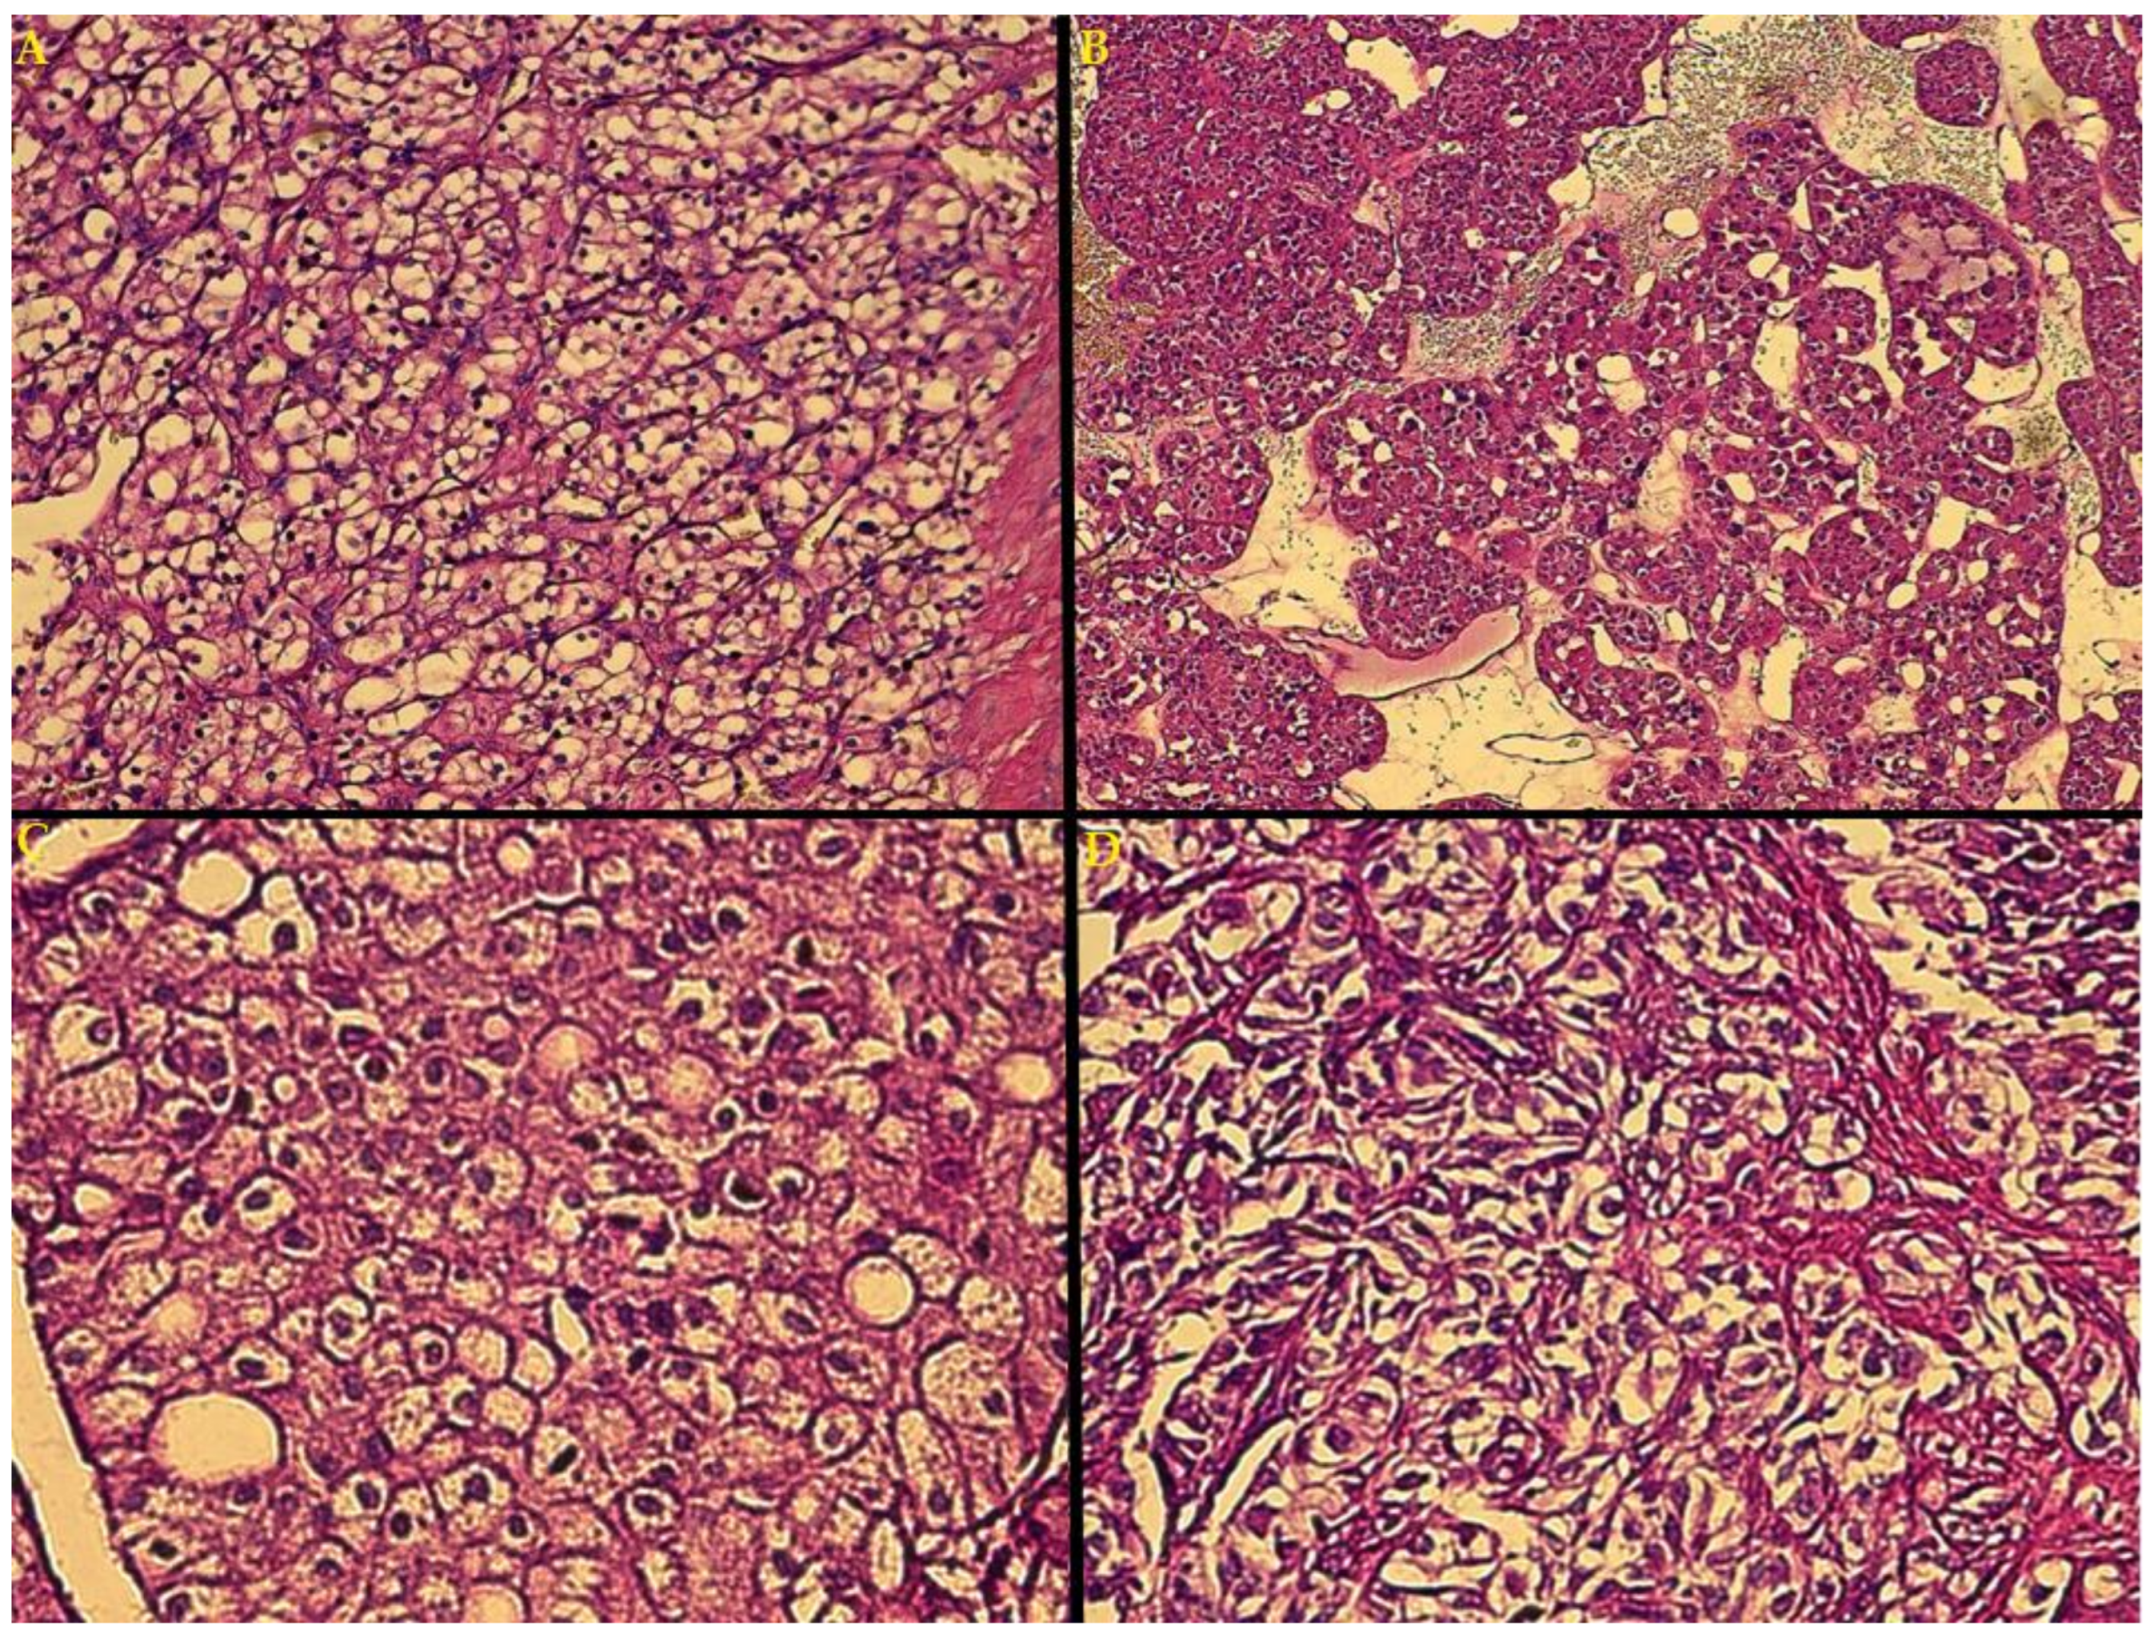

- Blastematous: diffuse, nodular and/or cord-like growth patterns of small, round and huddled blue cells, showing dark nuclei, diminished cytoplasm and frequent mitosis);

- Epithelial (tubules, papillae and glomeruli, similar to structures found in normal nephrogenesis, alongside more primitive rosette-shaped early tubular structures, and cysts lined with immature columnar/cuboidal cells);

- Stromal (resembling embryonal mesenchyme, spindle-shaped cells are seen on a myxoid stromal background, with a variety of patterns of differentiation and heterologous stromal elements, most commonly skeletal muscle in various stages of differentiation, including rhabdomyoblasts, but also cartilage, bone, fat or, more rarely, neuroglia and mature ganglion cells) [22,43].